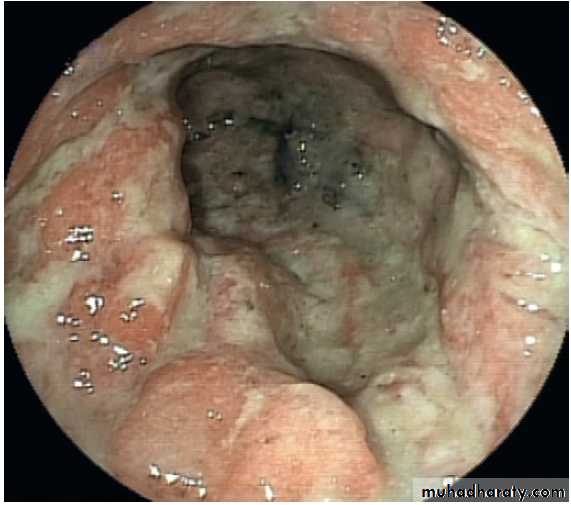

Severe reflux oesophagitis.

There is near-circumferentialsuperficial ulceration and inflammation extending up the gullet.